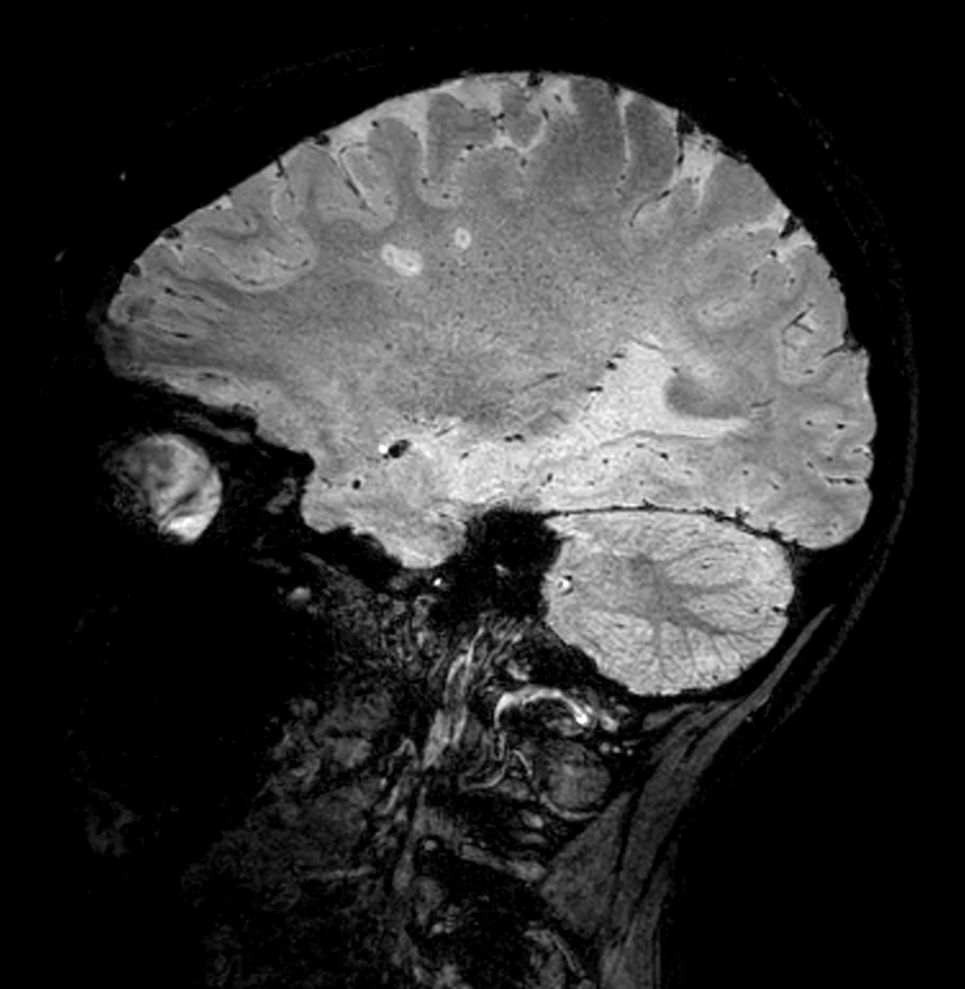

SWI sequence has a high sensitivity to enhance contrast for deoxygenated (venous) blood or calcium deposits. This may help, when used in combination with other clinical information, in the diagnosis of various neurological pathologies. 3D imaging lets you acquire high resolution data in multiple directions in one scan. Isotropic voxel size enables reformats in any plane without loss of resolution. FLAIR* requires offline post processing combining the contrast of 3D FLAIR and 3D SWI EPI into a single image. This enables the visualization of Central Vein Sign, mapping subcortical veins onto 3D FLAIR contrast images.